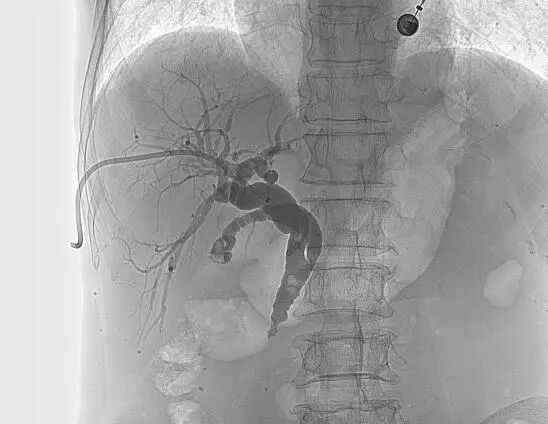

![]() 【如何治疗胆道梗阻?】 ![]() 胆道梗阻后,胆红素快速升高,会极大加重肝功能负担,最终导致肝功能衰竭。如何快速、有效的退黄成为梗阻性黄疸治疗的关键措施。介入治疗通过放置胆道引流管、胆道支架等手段能安全、高效退黄,以绝对微创的方式最大限度保护肝功能,为后续治疗创造机会。 ![]() ![]() 【经皮肝穿刺胆道引流术】 ![]() 在X线透视引导下穿刺扩张的肝内胆管并置入引流管,可以快速引流淤积的胆汁,减轻黄疸、保护肝功能,为后续治疗创造条件。优点在于见效快,能快速退黄和控制胆道感染。缺点在于需长期携带引流管并定期更换,生活质量降低,且胆汁无法进入肠道,影响消化功能。 ![]() ![]() ![]()

![]() 【经皮胆道支架置入术】 ![]() 胆道支架置入能很好地弥补经皮肝穿刺胆道引流术的不足之处,通过在胆管狭窄/阻塞处安置金属支架,解除胆道梗阻、恢复通畅,促进胆汁入肠,改善消化功能的同时无需长期带管,显著提高了生活质量,适合短期内有效解除胆道梗阻的患者(如恶性胆道梗阻)。 ![]() 低位胆道梗阻支架置入 ![]() 高位胆道梗阻支架置入 变身“小金人”并不可怕,找准病因,用对方法,也能轻松退黄。介入治疗应用于胆道梗阻多年,技术成熟,安全且高效。市四医院介入室能常规开展各类复杂胆道梗阻的介入治疗,高效扫“黄”,为肝功能保驾护航。